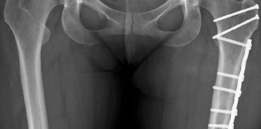

If the patient requires a derotational femoral osteotomy to correct the 36° anteversion, it is performed at this stage. A subtrochanteric osteotomy is executed, the femur is externally rotated to achieve a normalized anteversion of approximately 15°, and rigid fixation is achieved using a pre-contoured locking plate or a blade plate. Following the intra-articular and femoral work, the hip is reduced. The capsule is meticulously closed; a watertight closure is essential to prevent post-operative macro-instability and restore the proprioceptive function of the capsule. Finally, the greater trochanter is reduced and fixed using two or three fully threaded 4.5 mm cortical screws directed medially and slightly proximally toward the lesser trochanter.

Nerve injury, particularly to the sciatic nerve, is a risk during the posterior retraction required for the approach or secondary to hematoma formation. The incidence is approximately 1-2%, and it is usually a transient neurapraxia that resolves with conservative management and time. Progressive osteoarthritis is the ultimate mode of failure. In patients with unrecognized high-grade chondral damage at the time of surgery, the joint may continue to degenerate despite perfect structural correction. When the hip progresses to Tönnis grade 3 or the patient experiences intractable pain, the salvage procedure is a Total Hip Arthroplasty (THA). Fortunately, prior SHD does not significantly compromise the outcomes of subsequent THA, though hardware removal (trochanteric screws, osteotomy plates) may add complexity to the arthroplasty.